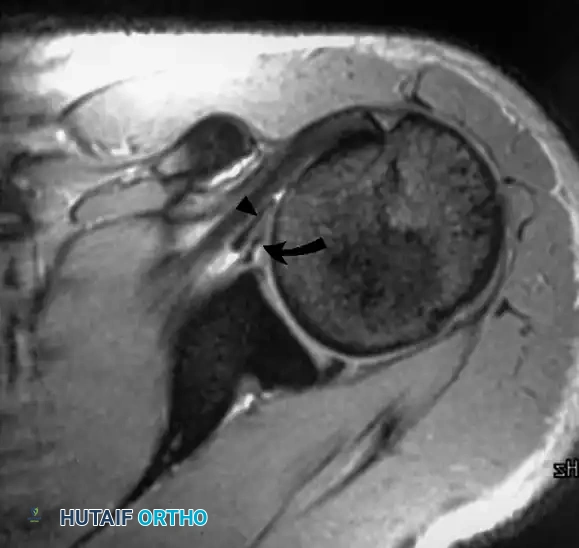

في نفس الموقع، تظهر هذه الصورة استخدام تقنية قمع الدهون. لاحظ كيف يظهر التمزق الكامل في وتر العضلة فوق الشوكة بوضوح تام (ممتلئ بالسوائل البيضاء الساطعة)، مما يسهل التشخيص الدقيق ووضع الخطة الجراحية.

توضح هذه الصورة المقطعية المحورية استخدام صبغة التباين داخل المفصل. يسمح هذا التمدد بتقييم ارتخاء المحفظة المفصلية واكتشاف أي إصابات في الشفا الغضروفي الأمامي (مثل آفة بانكارت) بدقة متناهية، وهو أمر حيوي لمرضى الخلع المتكرر.